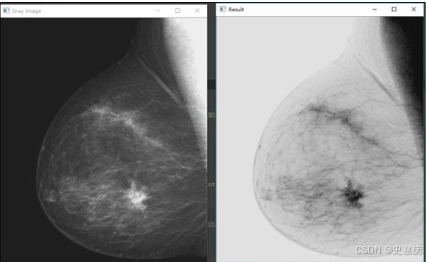

- 先直观感受一下灰度变换带来的变化。

灰度变换是图像处理中用于增强图像对比度或调整亮度的一种基础技术,通过对每个像素的灰度值进行数学映射来改善视觉效果。